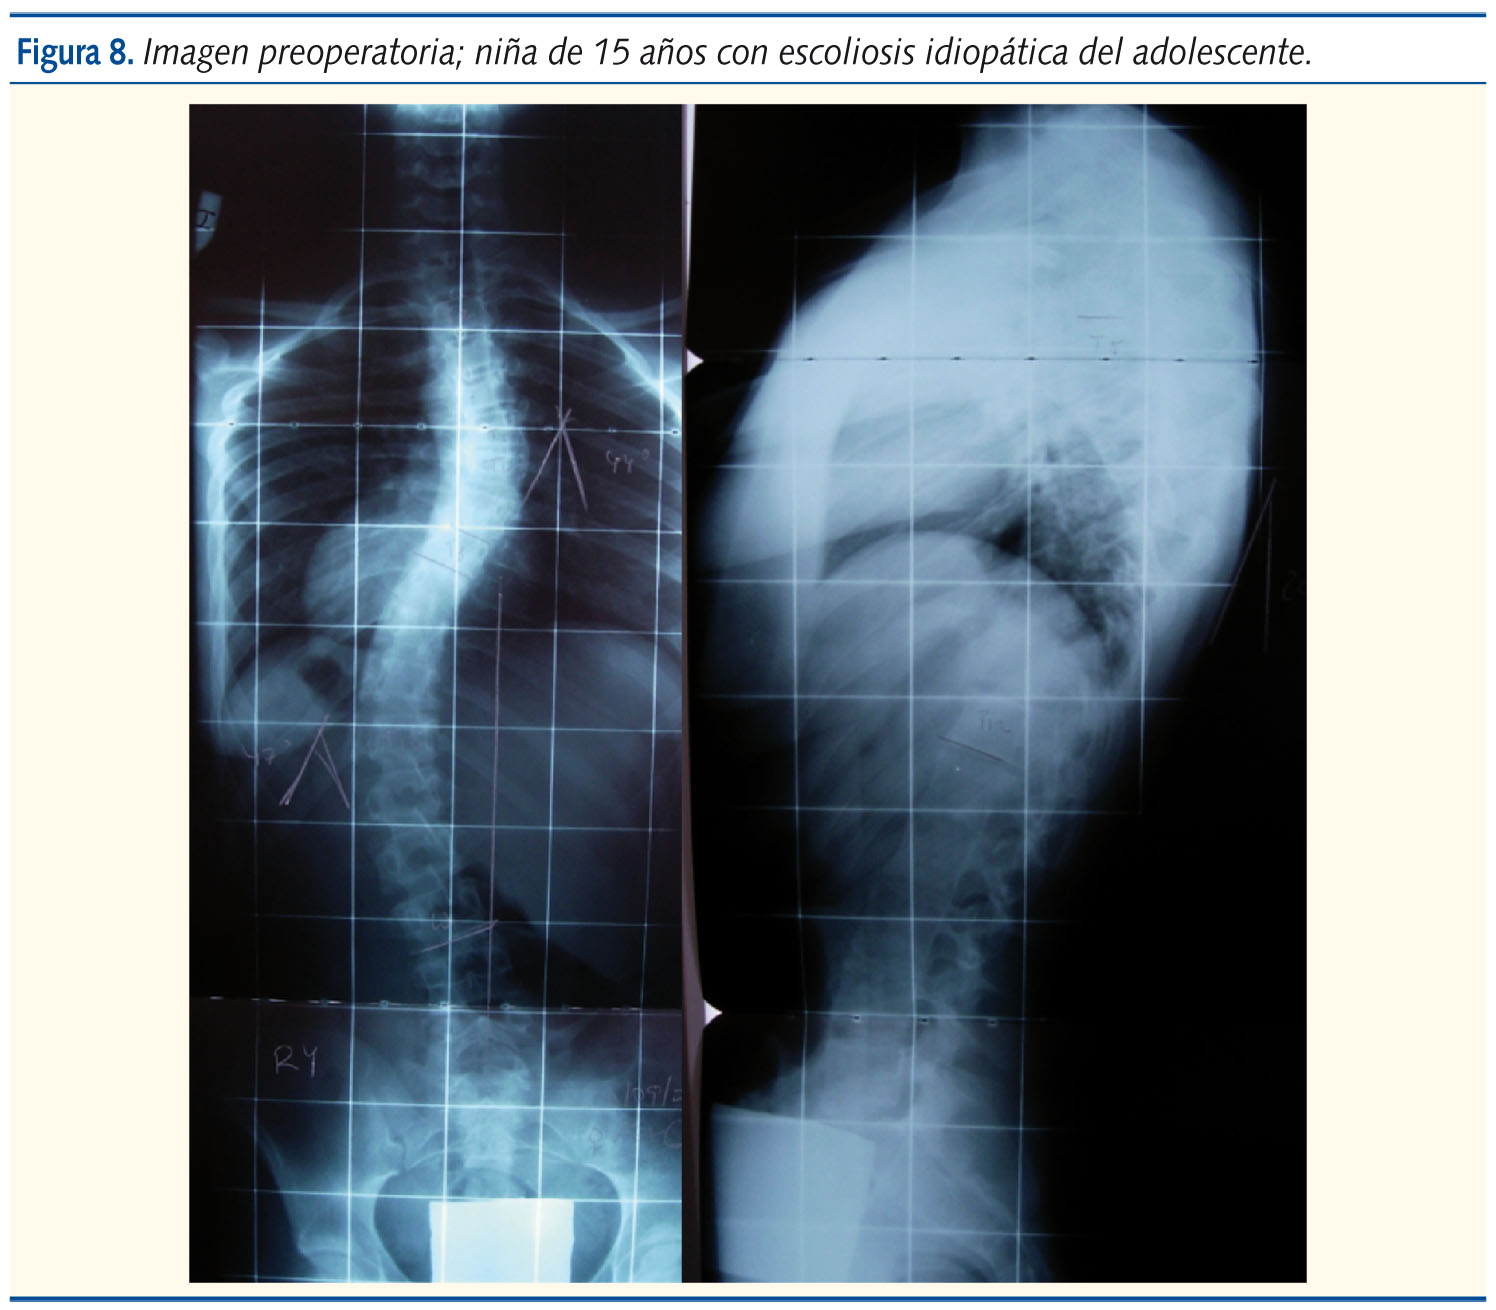

Las indicaciones de cirugía son todas las curvas de más de 45º en niñas premenárquicas con Risser 0 y Taner 2-3. Así mismo, las curvas de 40-45º que presenten progresión a pesar del corsé, y en el adolescente maduro con curva mayor de 50º. En la figura 7 se muestra el algoritmo de tratamiento de la escoliosis. La corrección de la deformidad se consigue con cirugía.

Generalmente, se realiza mediante la colocación de tornillos y barras en las vértebras implicadas en la deformidad, y con diferentes instrumentales se realiza la realineación (figuras 8 y 9). Se han mejorado las instrumentaciones en cirugía de columna y se consiguen mejores tasas de corrección y más anatómicas. También, la introducción de la monitorización neurofisiológica intraoperatoria ha añadido mayor seguridad durante las intervenciones.